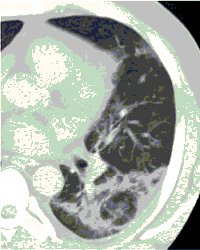

КТ имеет высокую чувствительность в выявлении изменений в легких, характерных для COVID-19. Применение КТ целесообразно для первичной оценки состояния ОГК у пациентов с тяжелыми прогрессирующими формами заболевания, а также для дифференциальной диагностики выявленных изменений и оценки динамики процесса. КТ позволяет выявить характерные изменения в легких у пациентов с COVID-19 еще до появления положительных лабораторных тестов на инфекцию с помощью МАНК. В то же время, КТ выявляет изменения легких у значительного числа пациентов с бессимптомной и легкой формами заболевания, которым не требуется госпитализация. Результаты КТ в этих случаях не влияют на тактику лечения и прогноз заболевания при наличии лабораторного подтверждения COVID-19. Поэтому массовое применение КТ для скрининга асимптомных и легких форм болезни не рекомендуется.

3. Применение лучевых методов у пациентов с симптомами ОРВИ легкой степени тяжести и стабильном состоянии пациента, возможно только по конкретным клиническим показаниям, в том числе при наличии факторов риска, при условии достаточных технических и организационных возможностей. Методом выбора в этом случае является КТ легких по стандартному протоколу без внутривенного контрастирования или РГ при ограниченной доступности КТ. Использование УЗИ в этих случаях нецелесообразно.

5. Рекомендовано проведение лучевого исследования пациентам при среднетяжелом, тяжелом и крайне тяжелом течении ОРИ с целью медицинской сортировки, оценки характера изменений в грудной полости и определения прогноза заболевания:

- выполнение КТ легких без внутривенного контрастирования в стационарных условиях или в амбулаторных - при показаниях к госпитализации;